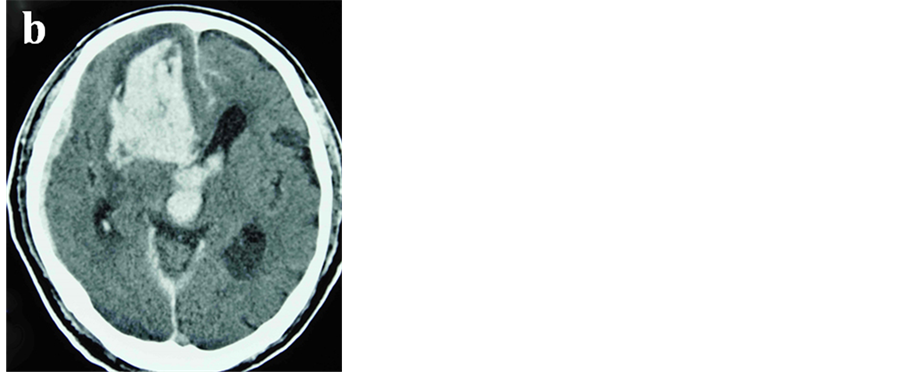

A 74-year-old man was transferred to our institute with severe impairment of consciousness. On admission, his Glasgow Coma Scale was 4 (E1V1M2) and he exhibited partial loss of brain stem reflexes. CT scan showed a large hematoma in the right frontal lobe with subdural and intraventricular hemorrhage. A more noteworthy finding was that suspicious vascular dilatation was located next to the intracerebral hematoma (Figure 1). Digital subtraction angiography (DSA) disclosed the presence of the dural arteriovenous fistula (dAVF) at the right anterior cranial fossa and fed mostly by the bilateral anterior ethomoidal arteries and partially by the falcine branch of the left middle meningeal artery, and the dAVF drained into the frontal cortical vein with a large venous pouch which coursed to the superior sagittal sinus (Figure 2).

Figure 2. Left (a) and right (b) carotid angiograms showing dAVF of the anterior cranial fossa fed by the bilateral ethmoidal arteries and the falcine branch of the left middle meningeal artery, furthermore demonstrating the cortical venous drainage and the huge venous pouch.